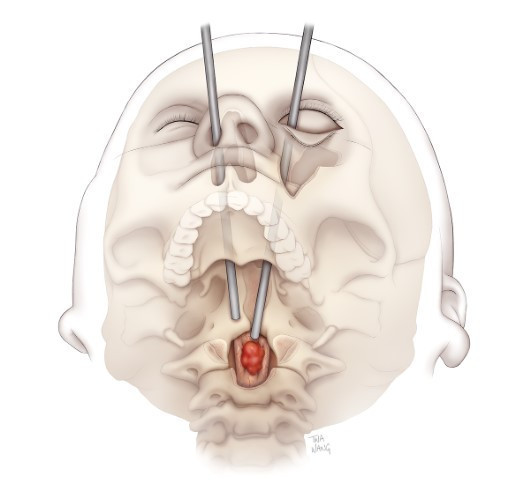

UMMC beyin cerrahı Dr. Mohamed Labib liderliğindeki ekip, ‘transorbital’ cerrahi yaklaşım kullanarak bu zorlu vakayı ele aldı. Bu yöntemle cerrahlar, göz çukurunun altından girerek omuriliğe doğrudan bir koridor oluşturdu. Dr. Labib, “Bu teknik sayesinde normalde ulaşılması imkânsız veya son derece riskli olan bir tümörü çıkarmayı başardık” dedi.

Labib’e, yüz plastik ve rekonstrüktif cerrahı Dr. Kalpesh T. Vakharia eşlik etti. Vakharia, Flores’in göz çukurunun altını ve elmacık kemiğinin bir kısmını çıkararak görünmeyen bir cerrahi erişim yolu oluşturdu. “Dışarıdan hiçbir iz kalmaması için özel olarak planladık” diyen Vakharia, operasyon sonrası göz çukurunun altını titanyum plakayla, yanağı ise hastanın kalçasından alınan kemikle yeniden inşa etti.

Flores’in tedavisi, yalnızca omurgadaki tümörle sınırlı değildi. Beyin sapına baskı yapan ikinci bir tümör de kafatası ve burun boşluğundan yapılan iki ayrı operasyonla çıkarıldı. Baş ve boyun cerrahı Dr. Andrea Hebert’in yer aldığı multidisipliner ekip, bu tümörlerin nüksetme ihtimaline karşı radyoterapi uygulaması da yaptı.